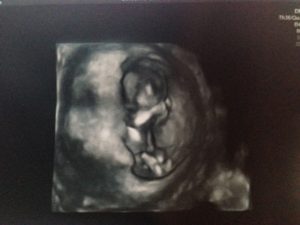

今回のエコーでは4センチまで成長していました!

今回のエコーでは、前回の2センチから2倍の成長している4センチのエコー写真をもらいました!

まだわからないかな?と思っていましたが、体全体がわかり、本当にゆりかごの中で育っているという、理想的な位置取りで写真が撮られていました。